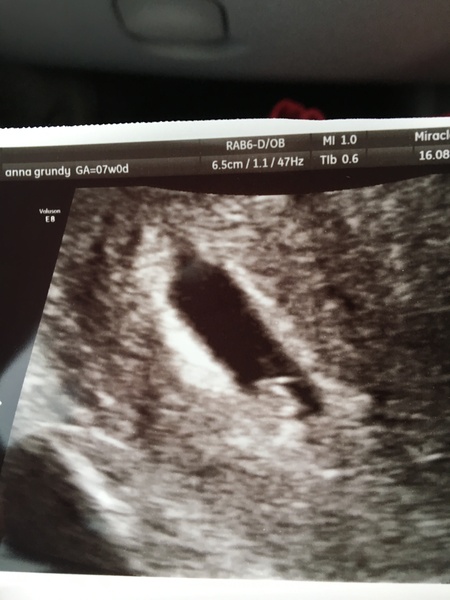

crispydumpling · 22/08/2017 12:49

Had an early scan last week and saw the heartbeat. I'm still finding it hard to believe that I'm pregnant, the only symptoms I have are nausea which comes and goes and a really strong hankering for pickled jalapeños!

Great scan pic crispy glad all is well and that your not experiencing sickness like last time!

@crispydumpling hurrah! I was wondering how you were! Cute pic! Congratulations xxx

@crispydumpling congrats on the scan! 😊 Time is going to go so slowly for me until I have mine on Thurdsay!!

Congrats @crispydumpling! Great picture and glad you're feeling ok! Sorry if you've already said this but how far along are you in that scan?